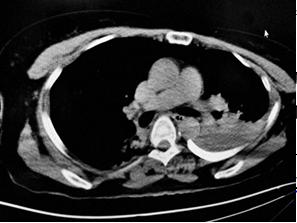

肋軟骨骨折 Ct

肋軟骨骨折 Ct のギャラリー

胸部外傷的急診患者 首先要想到這4類診斷 急診醫學影像 壹讀

胸部外伤看肋骨 诊断中这个建议最好写上 影像ppt

肋骨骨折 你漏诊了吗 螺旋ct三维重建在胸廓骨折中的应用价值